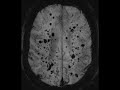

Multiple Cavernoma Syndrome

There are innumerable foci of increased susceptibility through both cerebral hemispheres, the cerebellum, and the brainstem. The largest lesion located in the periventricular white matter of the left frontal lobe has a popcorn appearance with peripheral areas of intrinsic T1 hyperintensity compatible with intralesional hemorrhage. The differential diagnosis includes multiple cavernoma syndrome, amyloid angiopathy, and microhemorrhages related to diffuse axonal injury. Given the brainstem involvement and the classic appearance of the lesion in the left frontal lobe for cavernoma, the best diagnosis in the case is multiple cavernoma syndrome. This is an autosomal dominant syndrome with variable penetrance. The mean bleeding rate is close to 1% per lesion per year. Cavernoma formation is also associated with brain radiation usually received in childhood with an average latency period of approximately 20 years.